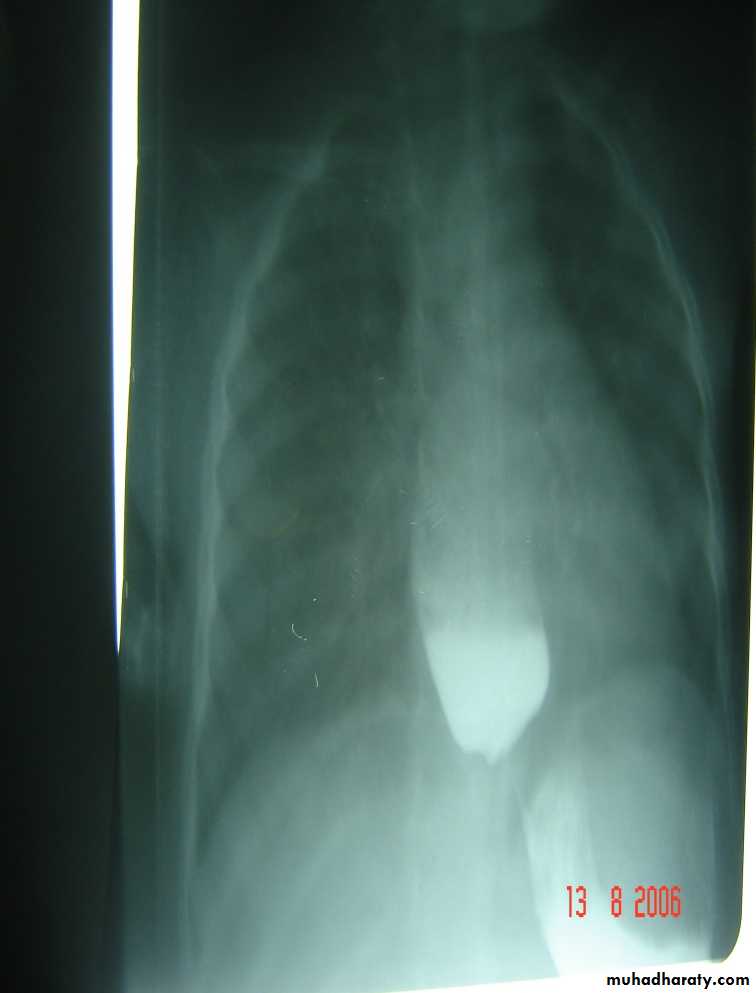

Respiratory Distress in the Newborn

Oesophageal Atresia and Tracheo-Oesophageal Fistula,